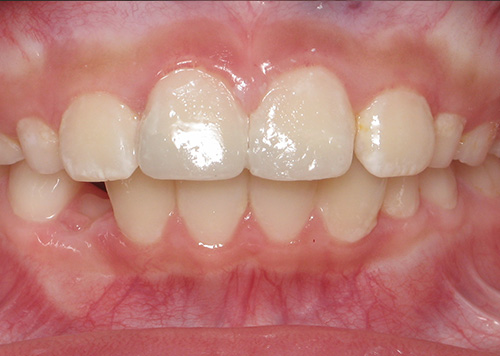

Smile Gallery

Orthodontic Treatment X-ray - Before

After Series of Teeth Extractions, Upper Left Canine Unerupted.

Ready to Start Ortho Treatment

Orthodontic Treatment X-ray - After